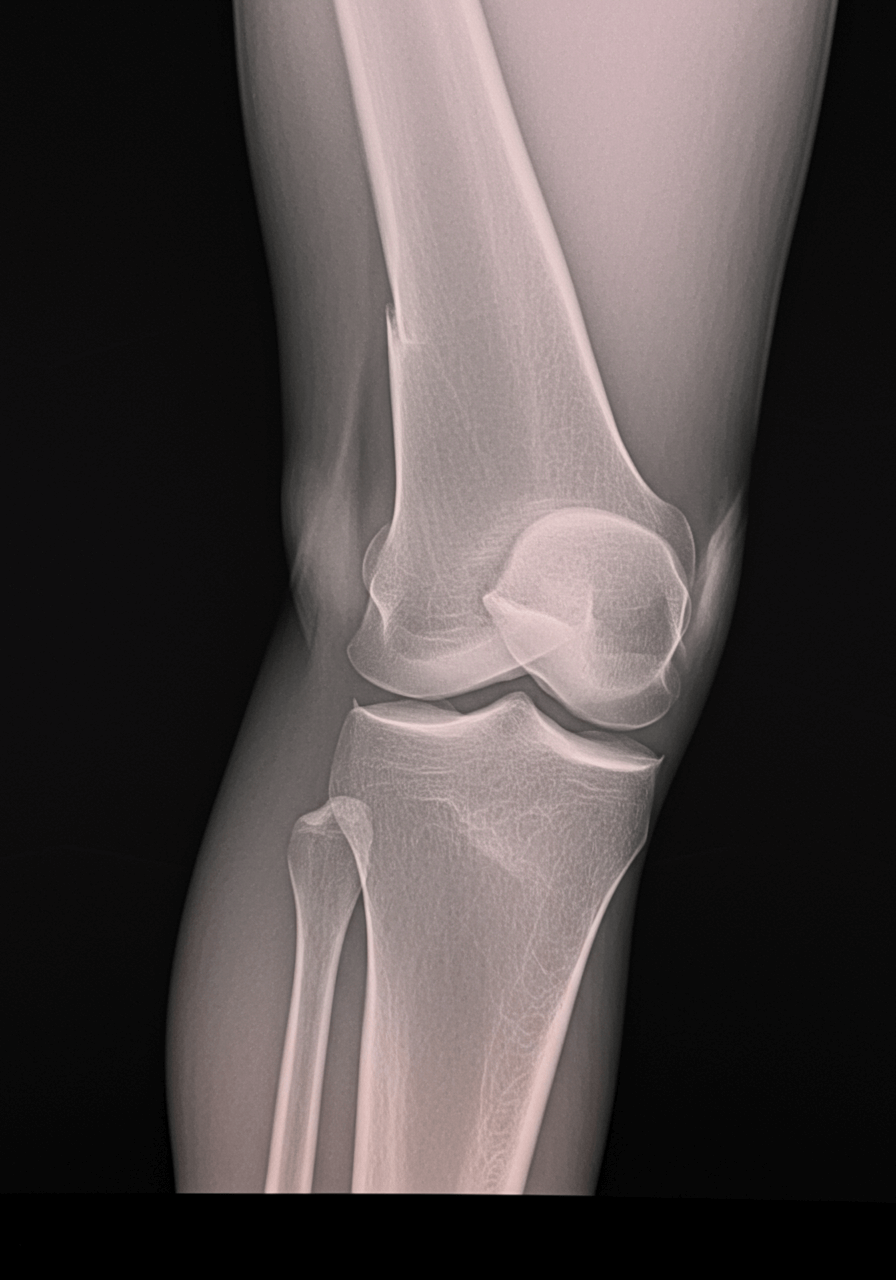

4. 무릎 통증 진단 방법 🔬

무릎 통증의 원인을 정확히 진단하기 위해 의사는 다양한 검사를 진행할 수 있습니다.

✅ 1) X-ray 검사

- 무릎뼈의 정렬 상태 및 골절 여부 확인

✅ 2) MRI (자기공명영상)

- 연골, 인대, 힘줄 손상 여부를 자세히 확인할 수 있음